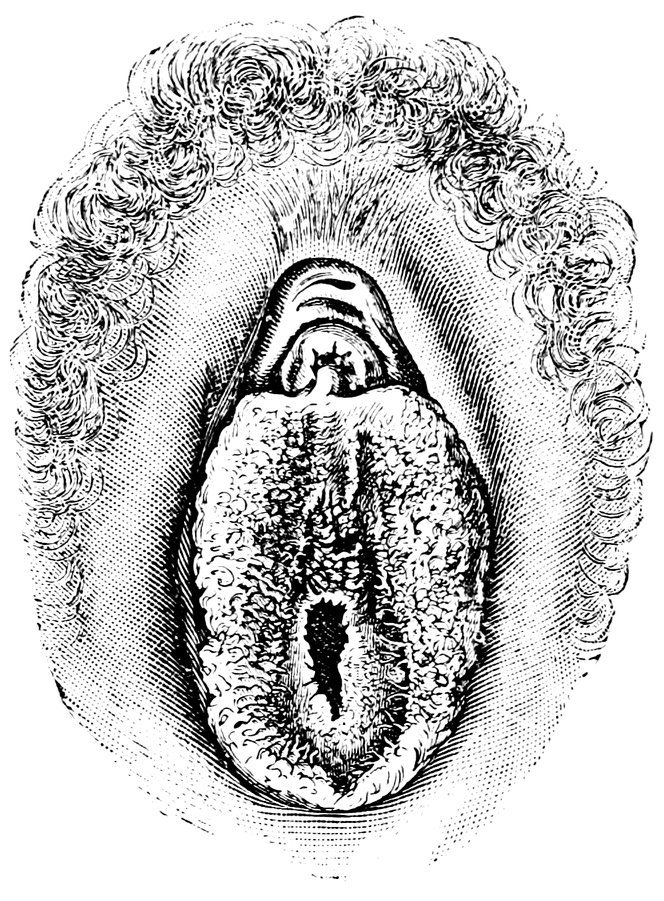

| 48. | The female pudendum, or vulva, with the labia majora | 204 |

| 49. | Vestibule of the vagina, with the labia minora or nymphæ, etc | 205 |

| 50. | The uterus, the left Fallopian tube and the left ovary, etc | 207 |

| 51. | Female internal genital organs in the fully developed state | 208 |